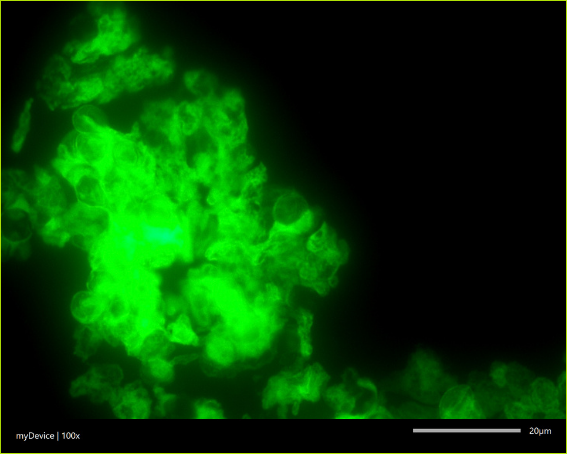

Cysty Pneumocystis jirovecii w materiale pobranym od pacjenta z pneumocystozą, znakowane metodą pośredniej immunofluorescencji.

Podczas operacji pobierano trzy rodzaje materiału: fragment tkanki nowotworowej, fragment sąsiedniej tkanki płuca, która makroskopowo nie wyglądała na zmienioną chorobowo, oraz wydzielinę z dolnych dróg oddechowych. Następnie za pomocą metody PCR poszukiwano DNA Pneumocystis jirovecii w materiale pobranym od pacjenta. Detekcja oparta na metodach molekularnych umożliwia wykrycie patogenu nawet przy niskiej intensywności zarażenia, którą charakteryzuje się kolonizacja.

Zastosowano metodę nested-PCR, w której amplifikowano fragmenty genów mitochondrialnych grzyba (mtLSU rRNA oraz CYB). Następnie przeprowadzono genotypowanie poprzez analizę polimorfizmów pojedynczych nukleotydów (SNP), co pozwoliło na identyfikację konkretnych szczepów patogenu.